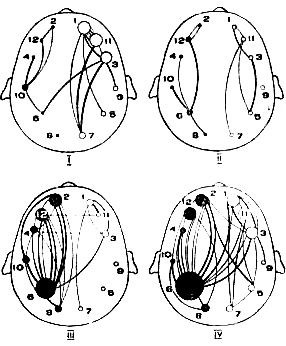

В результате таких наблюдений Пенфилд уточнил вопрос о речевых областях коры больших полушарий — они показаны на рис. 6.

Рис. 6. Карта речевых зон У. Пенфилда. Штриховкой в клетку показаны речевые зоны: слева — передняя (Брока), справа — задняя (Вернике) и сверху — добавочная. Цифрой 1 обозначена передняя центральная извилина (область двигательных проекций), цифрой 2 — задняя центральная извилина (область чувствительных проекций).

Кроме зоны Брока (которую он назвал передней речевой областью) и зоны Вернике (задняя речевая область), Пенфилд обнаружил дополнительную, или верхнюю, речевую область, которая не имеет таких определенных функций, как передняя и задняя речевые области, а играет вспомогательную роль. Ему удалось также показать тесную взаимосвязь всех трех речевых областей, которые действуют как единый речевой механизм. Когда у больного удаляли одну из речевых зон коры, возникавшие при этом нарушения речи через некоторое время становились меньше (хотя и не проходили полностью). Это означает, что оставшиеся речевые области брали на себя в какой-то мере функции удаленной речевой зоны. В этом проявляется принцип надежности в обеспечении чрезвычайно важной для человека речевой функции. Речевые области в этом отношении отличаются от многих других зон коры. Если, например, удаляется часть коры зрительной или слуховой областей, то нарушенные функции восстановить невозможно.

В наблюдениях Пенфилда и его сотрудников выявилась также неодинаковая роль речевых областей. Сроки и степень восстановления речи после удаления той или иной речевой зоны показывают, насколько велико значение данной зоны в осуществлении речевой функции. Оказалось, что легче и полнее речь восстанавливается при удалении верхней речевой зоны — значит, она действительно играет второстепенную роль.

При удалении зоны Брока нарушения бывают стойкими и остаются очень значительные дефекты, по все же речь может быть восстановлена. При удалении зоны Вернике, и особенно если затронуты подкорковые структуры мозга, наступают наиболее тяжелые, часто необратимые расстройства речи. Это показывает ведущую роль передней и задней речевых областей для развития и сохранения речи — их утрата компенсируется только отчасти.

Рис. 8 иллюстрирует последовательность включения различных речевых областей во время протекания речевого акта. Весь этот сложный процесс является саморегулирующимся, иными словами, одно звено акта автоматически включает следующее.

Рис. 8. Схема взаимодействия речевых отделов коры во время произнесения слова: 1 — зона Вернике, 2 — зона Брока, 3 — проекционная двигательная зона, 3а — проекционная чувствительная зона. Стрелки показывают направление распространения импульсов; i обозначает поток импульсов к речевым мышцам.

При нормальной речи работа обоих полушарий согласована очень точно. Ленинградские физиологи В. В. Беляев, И. В. Данилов и И. М. Черепанов изучали, как работают симметричные точки в правом и левом полушариях мозга человека в состоянии покоя и когда он говорит: ученые записывали биотоки мозга и проводили потом математическую обработку этих записей. Они нашли, что у здоровых людей всегда — и в покое, и во время речи — деятельность симметричных точек в лобных, височных и затылочных областях в обоих полушариях точно согласована, но протекание нервных процессов в левом полушарии на 3–4 тысячные доли секунды опережает течение процессов в правом. У больных с заиканием эти авторы обнаружили расхождение во времени деятельности симметричных пунктов до 44 миллисекунд, при этом правое полушарие начинало опережать левое! Эти различия хорошо видны на приводимых кривых (рис. 9 и 10).

Рис. 9. Кривая, показывающая работу симметричных точен в левом и правом полушариях мозга во время речи. Пунктиром показано течение процесса в левом, сплошной линией — в правом полушарии.

Рис. 10. То же у больного с заиканием. Обозначения те же.